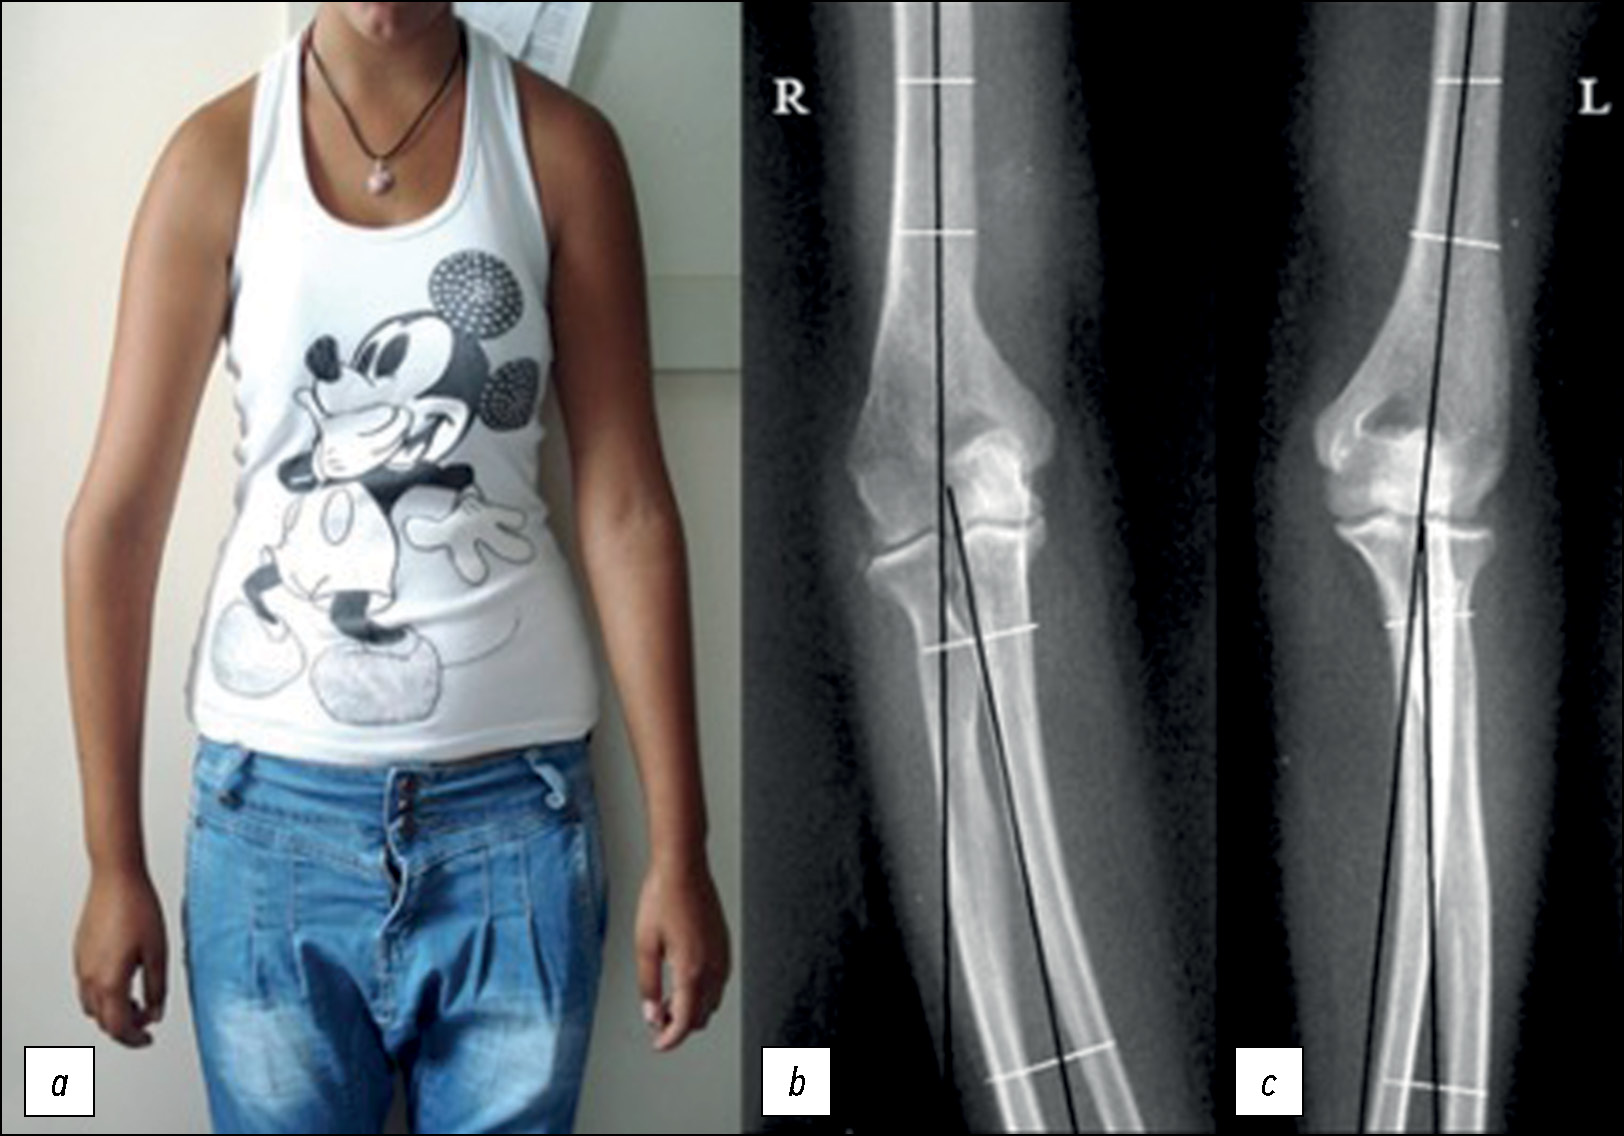

Рис. 3. a — клиническое фото, демонстрирующее деформацию правого локтевого сустава; переднезадние рентгенограммы правого (R) и левого (L) локтевых суставов: b — 12° varus-деформация на правом локте, c — 8° valgus-деформация на левом локте [6].

Fig. 3. a — clinical photograph at presentation shows obvious right cubitus varus deformity. Preoperative anteroposterior radiographs of the right (R) and left (L) elbows show a humerus-elbow-wrist angle of (b) 12° varus on the right elbow compared with (c) 8° valgus on the left elbow [6].